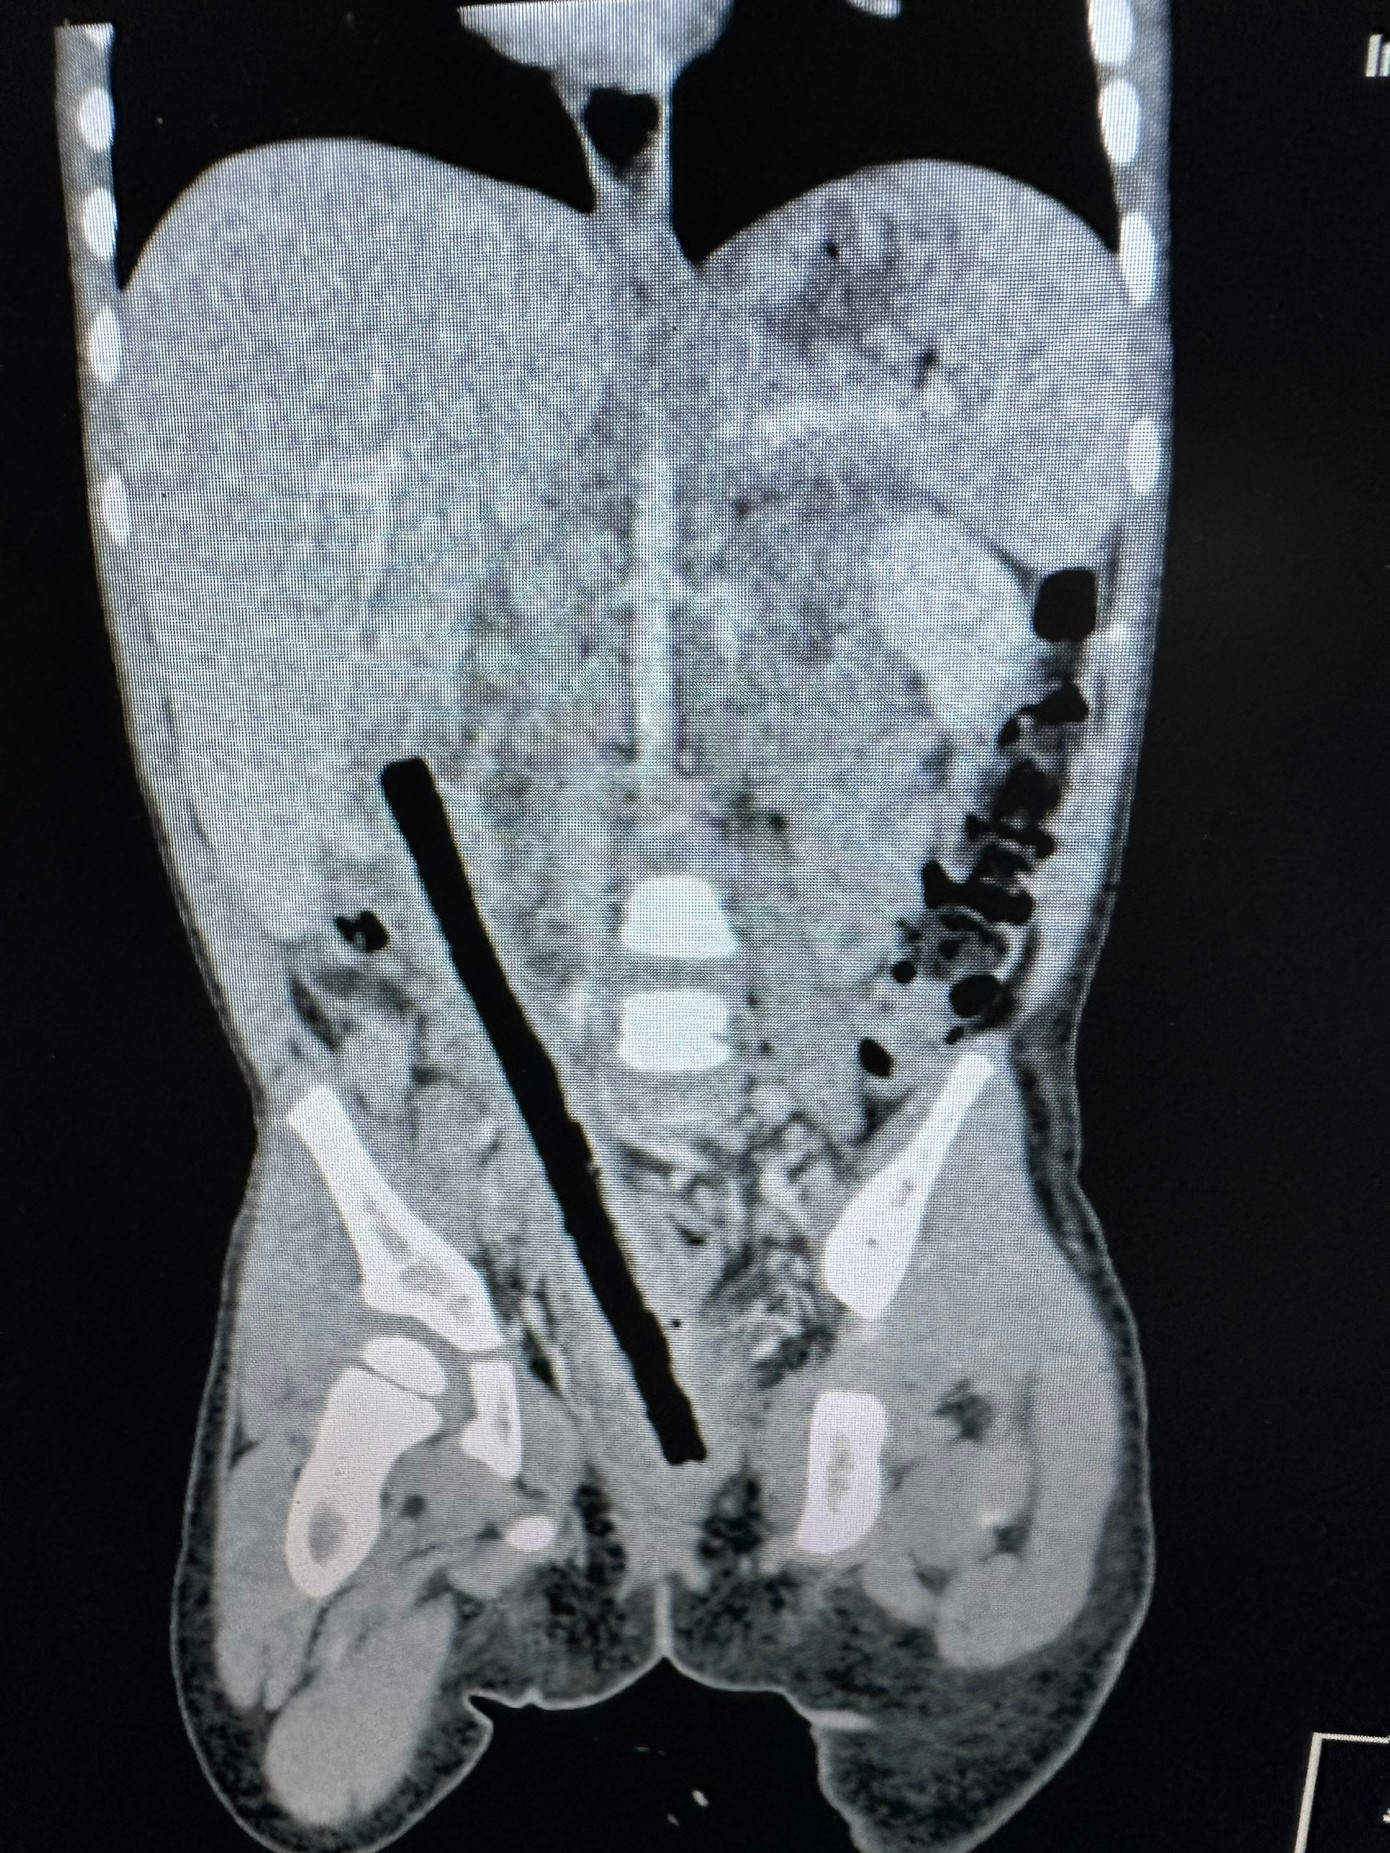

Hình ảnh dị vật là cành cây dài 16cm đâm xuyên bụng bé gái

Trong quá trình siêu âm, bác sĩ phát hiện khối lạ trong bụng nghi dị vật nên chuyển bé đến Bệnh viện Nhi Đồng 2. Kết quả CT-scan khiến các bác sĩ sửng sốt: một cành cây kích thước 1x16 cm xuyên từ trực tràng, ruột non đến gần gan bệnh nhi.